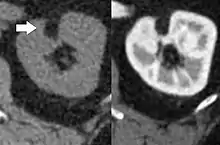

| Angiomyolipoma in both kidneys (arrows) in computer tomography. The tumours are hypodense (dark) due to fat content. | |